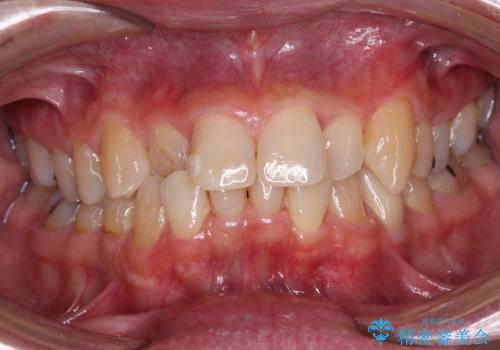

- 内側に倒れている前歯が擦れてしみるとのことで来院された患者様です。

削れていた部分は詰め物が入っていましたが、縁の部分がしみているようで、変色も目立っていたため、オールセラミッククラウンにて補綴治療を行うこととしました。

内側に倒れているため、下顎と強く干渉することが懸念されましたが、無理のない咬み合わせで、形態も左右対称に近い状態で仕上げることができました。